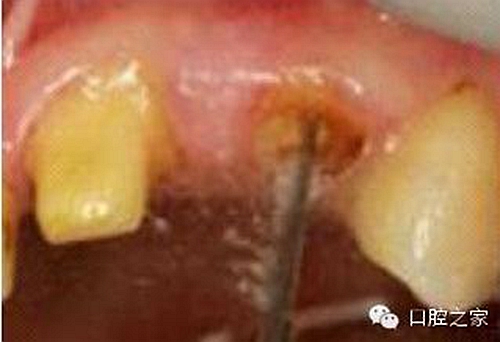

2. 清除根管壁殘留物

圖3:根管內(nèi)殘留物

圖4:超聲去除根管殘留物?! ?/p>

根管壁殘留物的存在直接影響著纖維樁的粘接和固位,是纖維樁脫落的主要原因之一。由于圓形的根管鉆和根管形態(tài)不完全一致,終鉆預(yù)備完成后大多情況下樁道側(cè)壁會有不同程度的牙膠和封閉劑等殘留物附著(圖 3)。因此,建議X線檢查根管預(yù)備情況,選用超聲潔牙機更換較細(xì)工作尖進(jìn)入根管,徹底去除樁道根管壁上附著的殘留物(圖4)。使用根管銼去除殘留物時,很難清除干凈;禁止使用牙膠溶劑如丁克除、氯仿等有機溶劑去除殘留物,以免破壞根尖區(qū)牙膠的封閉,或有機溶劑粘附于根管壁形成蠟?zāi)ざ绊懻辰印?#pages##